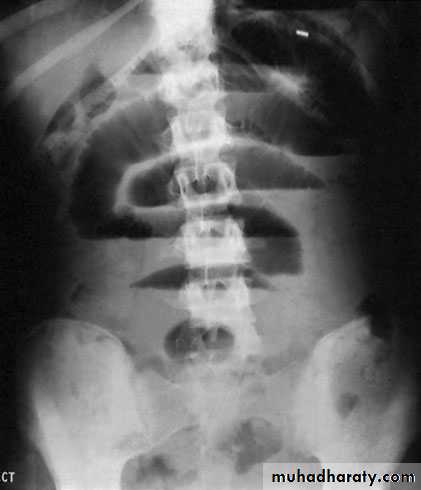

InvestigationImagingAs there is an enlarged rectum, often with distension of the colon over a variable length, a radiograph should be taken without prior bowel preparation, using a small quantity of water-soluble contrast to prevent barium impaction. There is usually gross faecal loading of the enlarged rectum and colon and, when a contrast examination is carried out, the width of the colon measured at the pelvic brim is usually more than 6.5 cm.

Complications of severe diseaseFulminating colitis and toxic dilatation (megacolon)Patients with severe disease should be admitted to hospital forintensive treatment. This occurs in 5–10% of patients. Thepatient will have severe rectal symptoms with systemic upset suchas weight loss and dehydration. In patients on intensive treatment such as steroids, there may befew symptoms. The diagnosis is confirmed by the presence on aplain abdominal radiograph of the colon with a diameter of morethan 6 cm. The condition must be differentiated from dysentery,typhoid and amoebic colitis. Plain abdominal radiographs shouldbe obtained daily in patients with severe colitis, and a progressiveincrease in diameter in spite of medical therapy is an indicationfor surgery

InvestigationsA plain abdominal film can often show the severity of disease.Faeces are present only in parts of the colon that are normal oronly mildly inflamed. Mucosal islands can sometimes be seen.

Severe attacksThese patients must be regarded as medical emergencies andrequire immediate admission to hospital. It is important to monitor vital signs (pulse, temperature andblood pressure). A stool chart should be kept.Increasing abdominal girth is a potential sign of megacolon developing.A plain abdominal radiograph is taken daily and inspectedfor dilatation of the transverse colon of more than 5.5 cm.